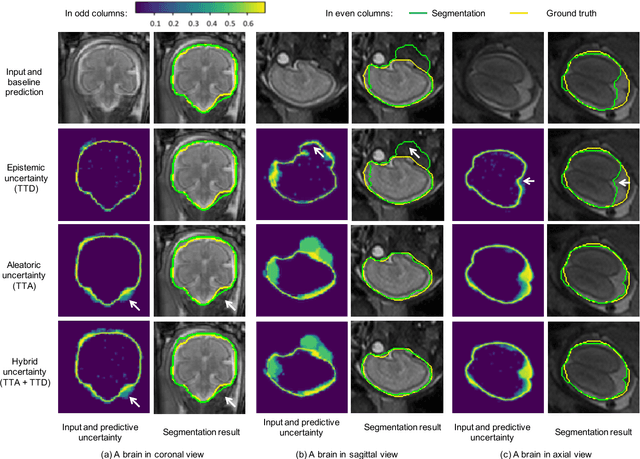

Despite the state-of-the-art performance for medical image segmentation, deep convolutional neural networks (CNNs) have rarely provided uncertainty estimations regarding their segmentation outputs, e.g., model (epistemic) and image-based (aleatoric) uncertainties. In this work, we analyze these different types of uncertainties for CNN-based 2D and 3D medical image segmentation tasks. We additionally propose a test-time augmentation-based aleatoric uncertainty to analyze the effect of different transformations of the input image on the segmentation output. Test-time augmentation has been previously used to improve segmentation accuracy, yet not been formulated in a consistent mathematical framework. Hence, we also propose a theoretical formulation of test-time augmentation, where a distribution of the prediction is estimated by Monte Carlo simulation with prior distributions of parameters in an image acquisition model that involves image transformations and noise. We compare and combine our proposed aleatoric uncertainty with model uncertainty. Experiments with segmentation of fetal brains and brain tumors from 2D and 3D Magnetic Resonance Images (MRI) showed that 1) the test-time augmentation-based aleatoric uncertainty provides a better uncertainty estimation than calculating the test-time dropout-based model uncertainty alone and helps to reduce overconfident incorrect predictions, and 2) our test-time augmentation outperforms a single-prediction baseline and dropout-based multiple predictions.